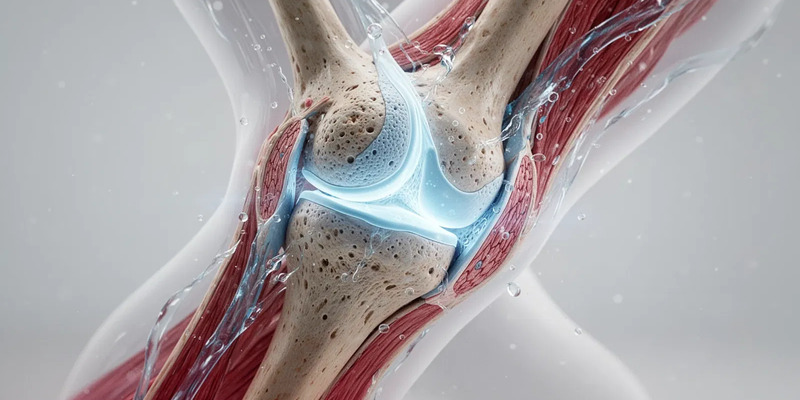

Wie Bewegung den Knorpel am Leben hält

Entgegen der alten Annahme, dass Belastung den Verschleiß beschleunigt, braucht der Gelenkknorpel moderate Bewegung, um gesund zu bleiben. Da er keine eigenen Blutgefäße hat, ernährt ihn die Gelenkflüssigkeit. Der rhythmische Druck beim Gehen wirkt wie eine Pumpe: Bei Belastung werden Abfallstoffe herausgepresst, bei Entlastung strömt nährstoffreiche Flüssigkeit ein. Dieser Zyklus ist überlebenswichtig für die Knorpelzellen. Bewegungsmangel unterbricht ihn – der Knorpel wird spröde und baut schneller ab.